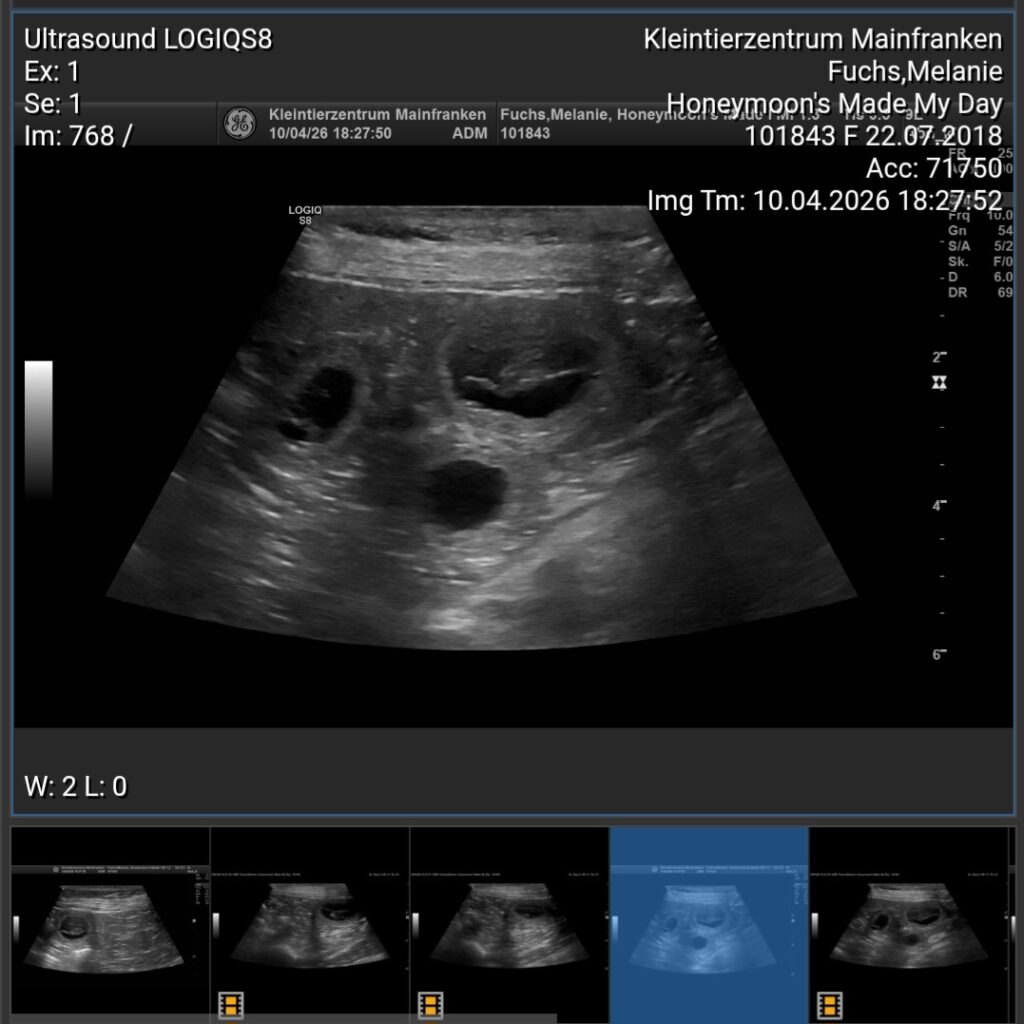

Choplin ist tragend. Der Ultraschall hat es gezeigt. Ach wie freue ich mich!

Am Donnerstag, 9. September waren wir zum Ultraschalltermin in der Klinik. Es sieht super aus! Die kleinen Würmchen bewegen sich und das Fruchtwasser ist auch in Ordnung. Wir erwarten unsere Welpen um den 12. Oktober – juhuuuu, wir sind so happy und aufgeregt!